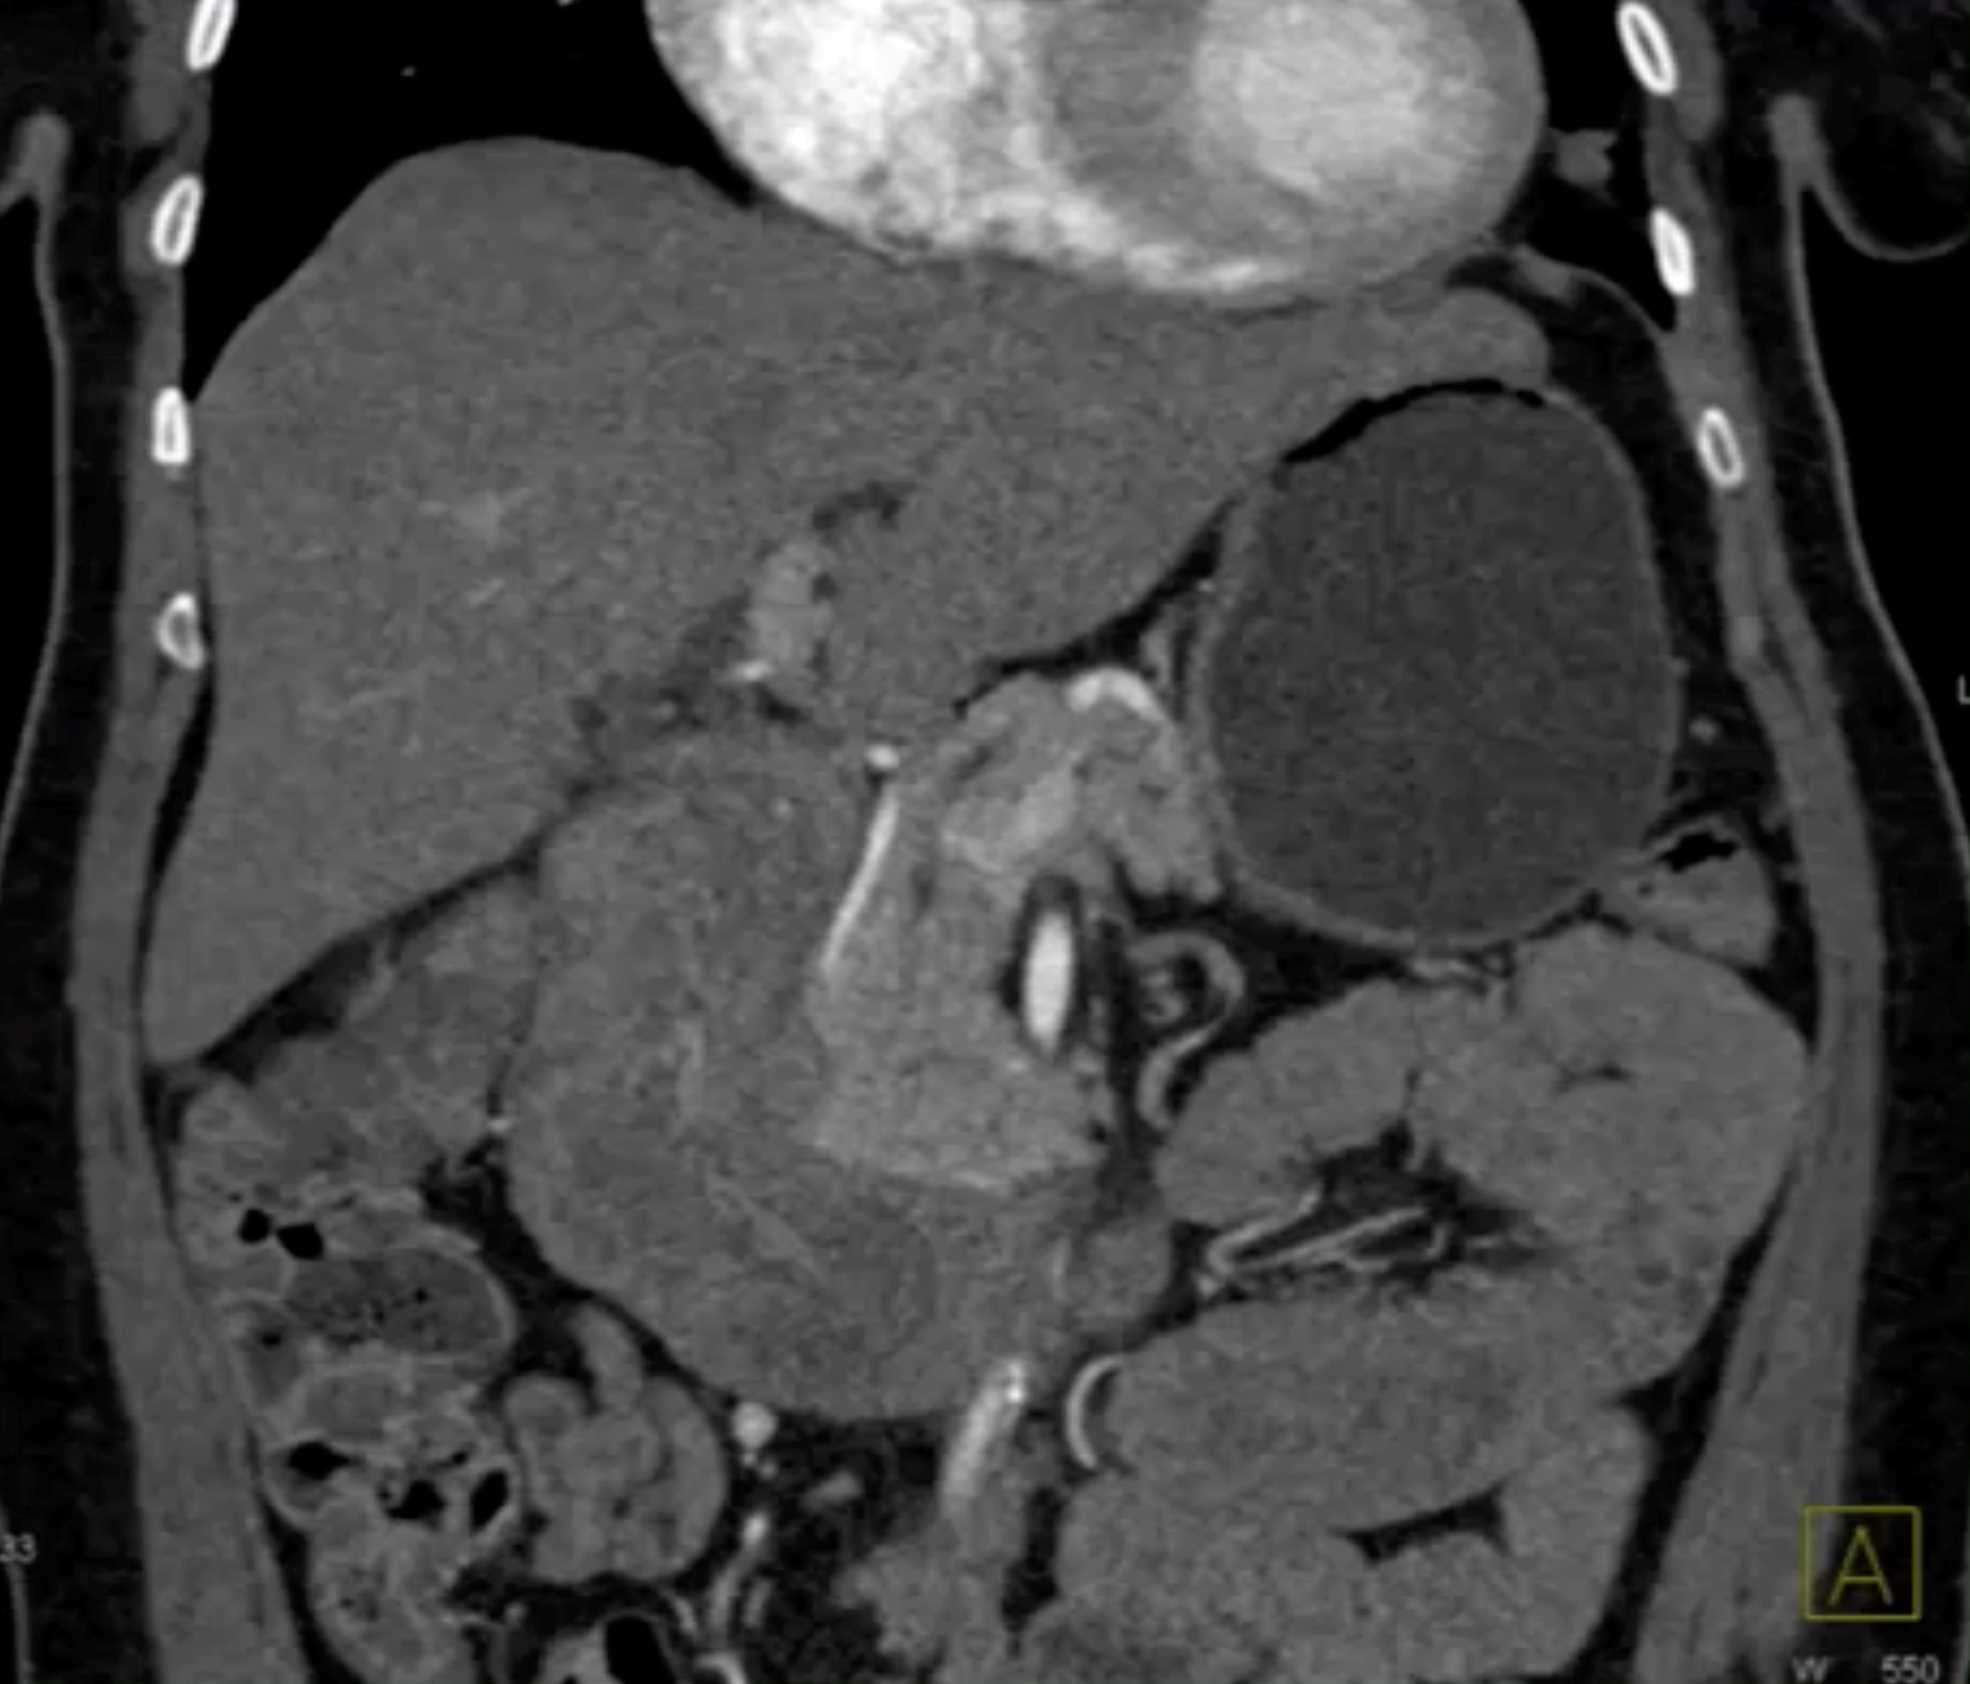

Lagre Gastric GIST Tumor